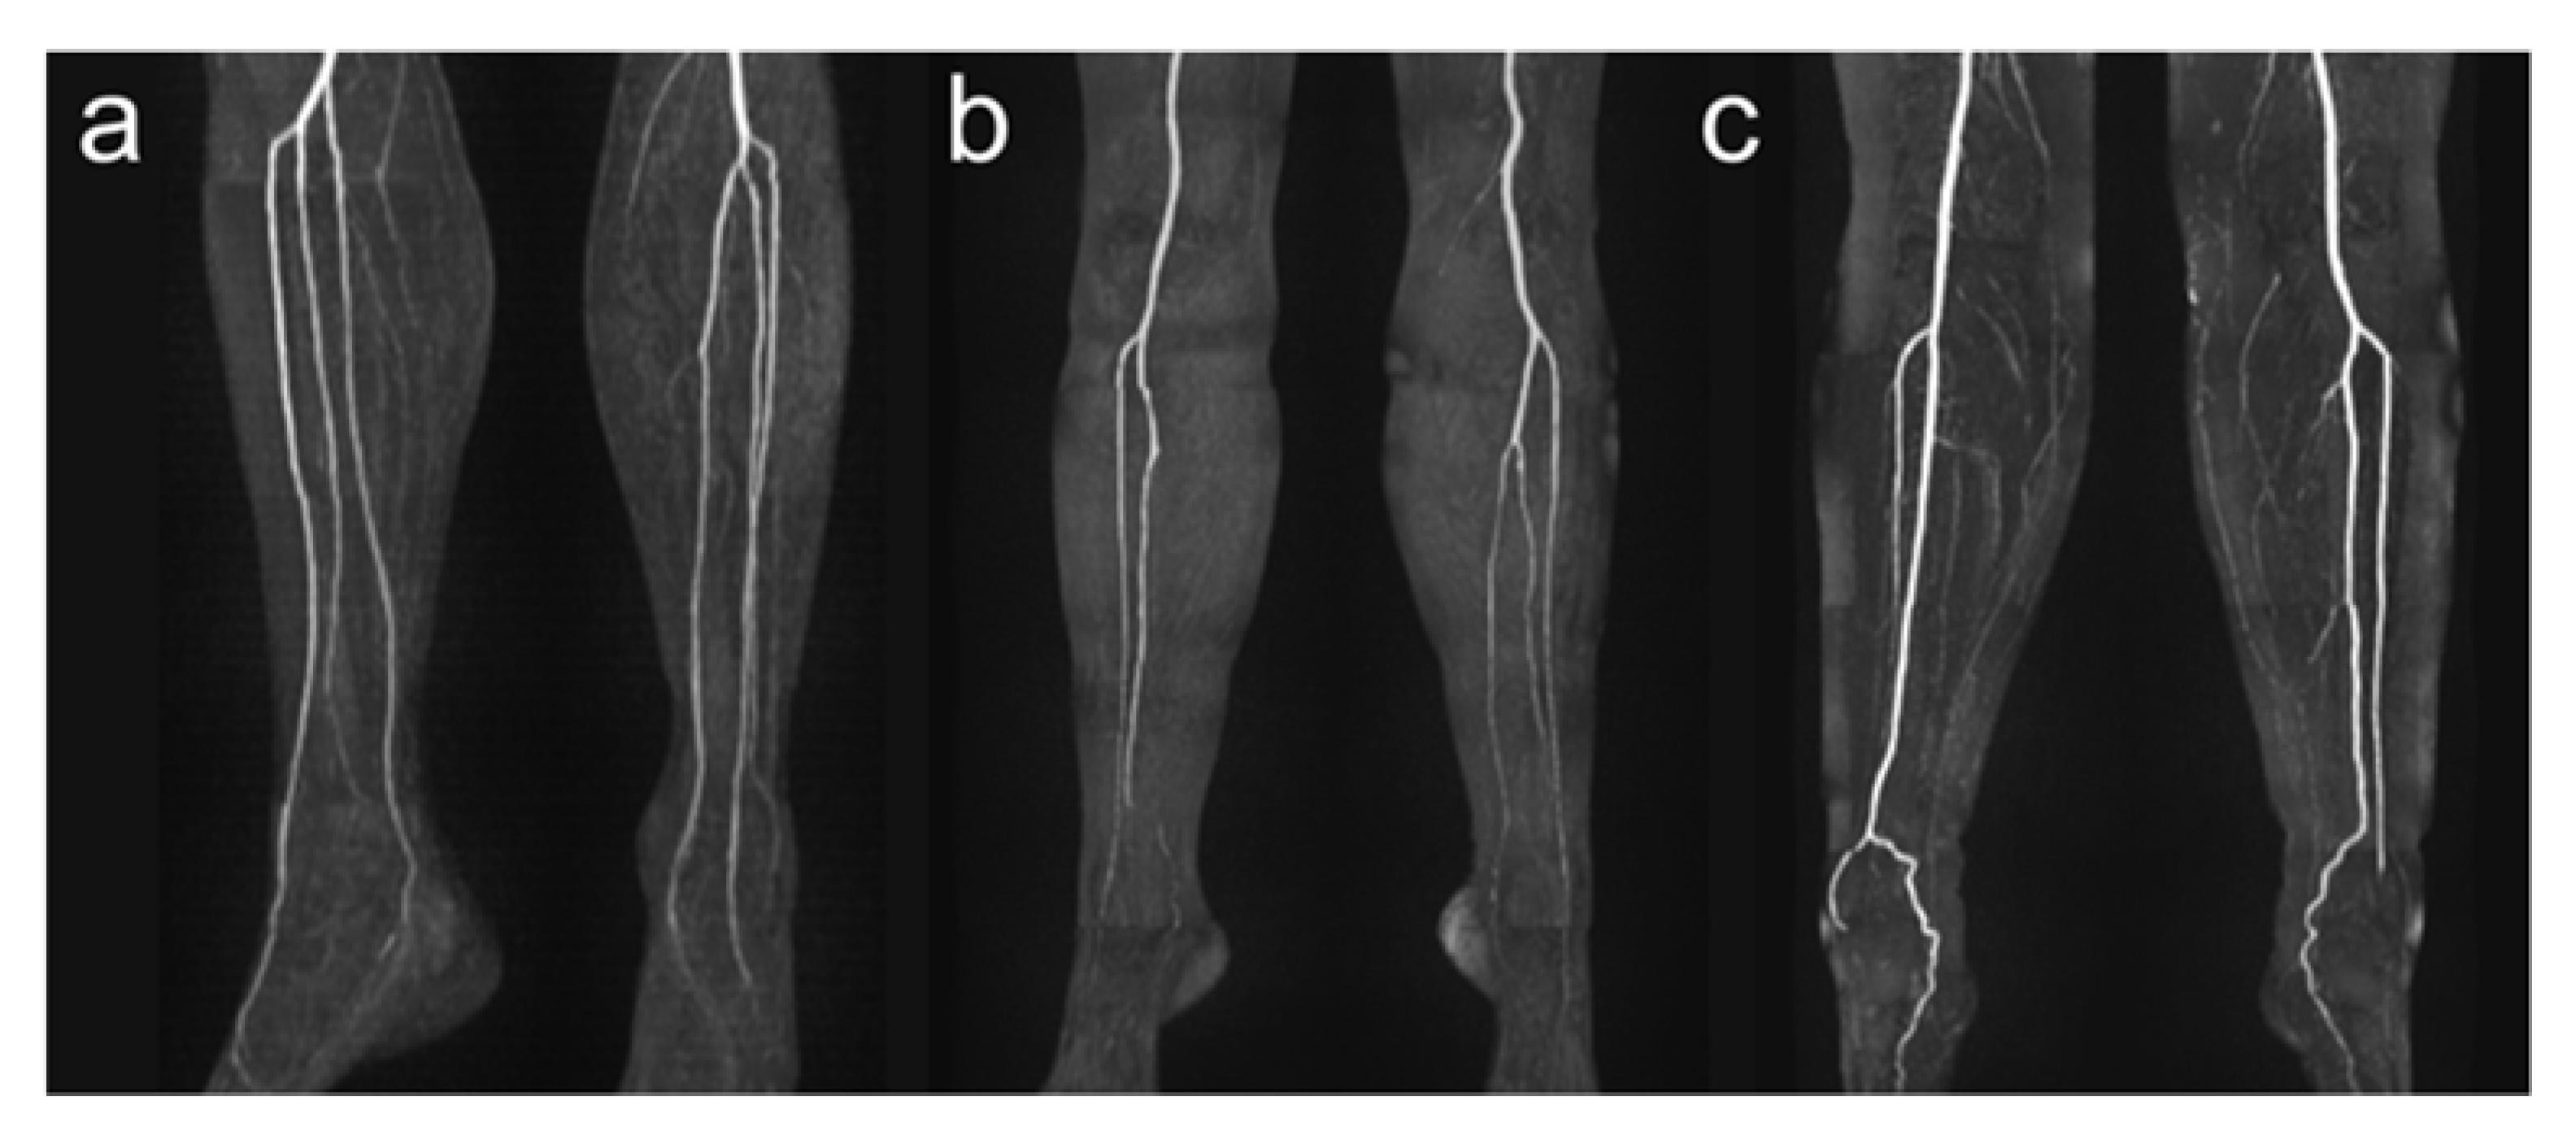

Figure 3.

Exemplary illustration of anatomical vessel variations of lower leg arteries. Panel (a) shows a type I-C according to Kim et al. [19] with the first exit of the PT below the knee joint with the subsequent exit of FA and AT via a common trunk. Panel (b) shows a hypoplastic PT (Type III-A) on the right side, and panel (c) shows a hypoplastic PT on both sides. Note the supply to the foot in these cases from the FA.